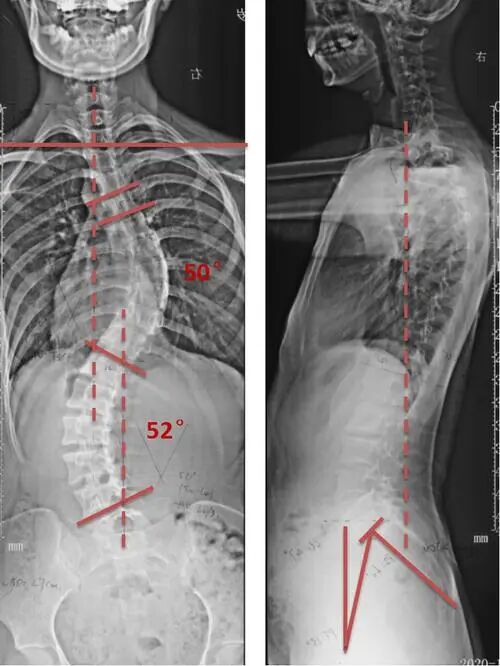

图片